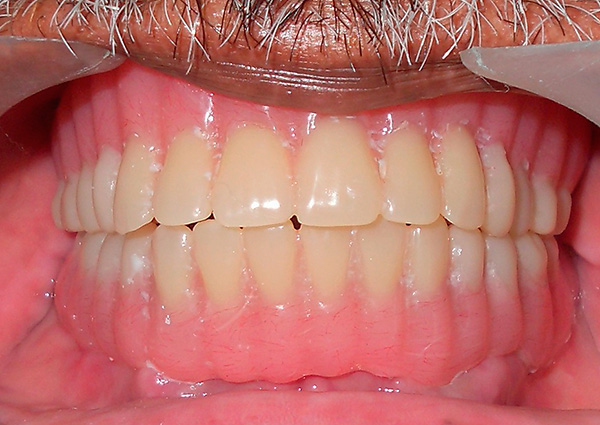

Deve-se ter em mente que o conceito de "implantação basal", como tal, hoje é coisa do passado. Existe um protocolo de carregamento imediato, que inclui várias tecnologias para restauração dentária, dependendo do quadro clínico. É adequado para restaurações simples e múltiplas, incluindo a ausência completa de dentes - um exemplo correspondente é mostrado nas fotografias abaixo:

O protocolo de carregamento imediato implica a realização da operação em uma única etapa, bem como o carregamento instantâneo (imediato) da prótese - daí o nome (implantação de dentes com carga imediata, implantação em estágio único, sinônimos simultâneos e outros).

Esse protocolo também é usado para restaurações únicas, mas é mais adequado para pacientes com desdentamento completo ou falta de segmentos de dentes inteiros. Além disso, nos casos em que são observados processos atróficos no tecido da mandíbula, a técnica também pode ser aplicada através do uso de partes fortes e estéreis do osso (falaremos mais sobre isso mais adiante).